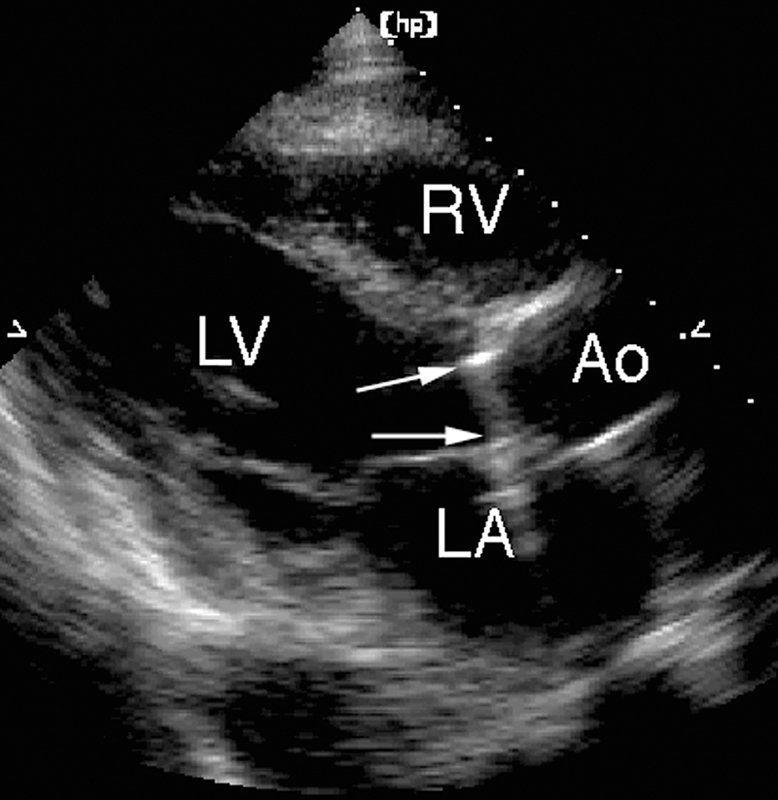

فحوصات تشخيصية لبعض امراض القلب والشرايين التاجية